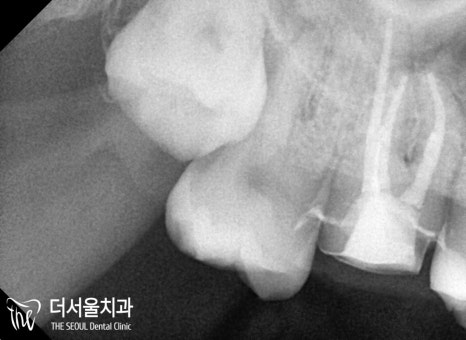

기존 보철을 벗겨보니

생각보다 심하게 퍼져 있는

이차우식을 확인할 수 있었는데요.

성남치과 에서 받는 모든 보철은

영구적으로 사용할 수 없기 때문에

주기적으로 내원을 하셔야 됩니다!!

이분께서는 안타깝지만,

이미 그런 시기를 놓치게 된것이죠ㅜㅜ